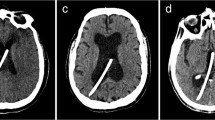

The diversity of ventricular dimensions was quantified using the frontal horn ratio (FHR) as described by Hahn and Rim (1976) [15]. This parameter was calculated as the distance between the anterior angles of the two frontal horns (bifrontal distance) divided by the transverse internal diameter of the skull measured along the same line used to assess the bifrontal distance (Fig. 2d).

Radioanatomical analysis of optimal ETV trajectories. Panel A: coronal view of the optimal ETV trajectory (yellow line) connecting the foramen of Monro and the floor of the third ventricle. Arrow indicates the midline. Insert: measurement of ETV entry point (yellow target) distance from Bregma in the coronal plane (“x”). Panel B: sagittal view of the optimal ETV trajectory depicted in “A”. Arrows indicate the coronal suture. Insert: distance of the ETV entry point (“y”) form the coronal suture (yellow arrow). Panel C: surgical view of a three-dimensional model created for the case shown in A and B. Optimal ETV trajectory (yellow bar) and entry point (yellow dot) correspond to case in “A” and “B”. Arrows mark the coronal suture. Inset: “x” and “y” represent entry point distance from the Bregma and coronal suture, respectively. Panel D: frontal horn ratio expressed as the distance between the frontal horns (“a”) and the internal diameter of the skull along the same line (“b”)

Assessment of optimal ETV entry points and trajectory

The optimal trajectory for a right-sided ETV was defined as the line connecting the floor of the third ventricle with the center of the foramen of Monro [8, 10, 16, 17] (Fig. 2a and b). The optimal ETV entry point was derived as the intersection of this trajectory with the level of the skin. The location of this entry point was recorded as the distance laterally from Bregma in the coronal plane perpendicular to the sagittal suture (x) and the distance anteroposteriorly from the coronal suture in the sagittal plane parallel to the sagittal suture (y) (Fig. 2a and b). Entry points posterior to the coronal suture were expressed as negative “y” values.

Assessment of optimal entry point

The third ventricle floor was accessible in all cases therefore establishing the optimal ETV trajectory was feasible in every patient. The average distance of the optimal entry point from Bregma were 29.2 ± 9.4 mm (mean ± standard deviation, range 17.3 to 47.2 mm) in the coronal plane (“x” coordinate) and −12.8 ± 5.6 mm (range: −7.4 to −24.5 mm) posterior to the coronal suture in the sagittal plane (“y” coordinate) which is comparable to the values found by Duffner [9] and Cheng [8]. Numeric coordinate values of the optimal entry point showed a good correlation with the FHR: with x = 85.8 FHR−13.3 (r 2 = 0.84, p < 0.001) and y = −69.6 FHR + 16.7 (r 2 = 0.83, p < 0.001). Further analysis using multivariate regression showed that with an increasing ventricle size, the optimal entry point seemed to migrate more lateral and posterior relative to Bregma (p < 0.05 for both x, y variables). Scatter plot of the optimal entry points (Fig. 3c) fitted well to a linear model: y = −0.76× + 4.85 (r 2 = 0.86, p < 0.001).

Optimal entry points are plotted in a Cartesian coordinate system with analysis of linear regression. Scatter plot of optimal entry point distances from Bregma in the midline along the coronal plane (A) and from the coronal suture in the sagittal plane (B) plotted against the frontal horn ratio (FHR). Note the linear correlation between the frontal horn ratio and both “x” and “y” variables. Panel C: labeling in the formulas follow Cartesian coordinate system reconstituting the skull surface with “0” indicating Bregma, “x” and “y” axis representing distances in the coronal and sagittal plane, respectively. Note the linear distribution of optimal entry points in a posterolateral direction with an increasing ventricle size. Linear equations with r 2 values are inserted in each graph; variable notations follow those in Fig. 2